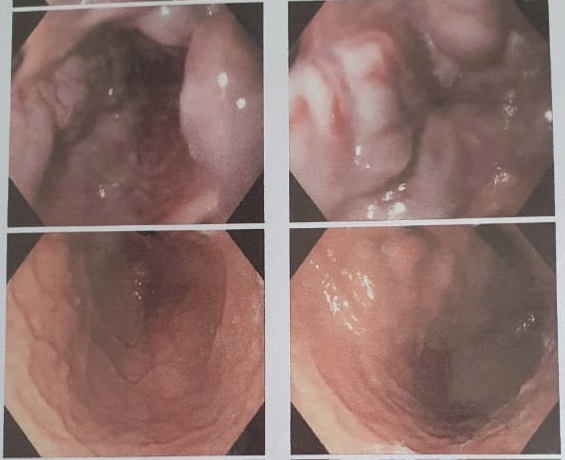

A vascular doppler sonography disclosed multiple cysts in right liver lobe, splenomegaly and widened caliber of portal venous which indicate portal hypertension. An abdominal CT scan with contrast was also conducted. Hepatomegaly, dilatation of intrahepatic biliary duct particularly at the right lobe, the largest cyst measured 5,47 x 5,77 x 5,54 cm, suggested Choledochal cyst type V (Caroli’s disease, according to Todani’s classification), cholangitis and cholecystitis were found (Figure 3). There were also splenomegaly and right nephrolithiasis.

Figure 3: Abdominal CT scan.

Upper gastrointestinal endoscopy (Figure 4) demonstrated the presence of grade 3-4 gastroesophageal varices, from corpus gastric proximally to the four columns of esophagus without active bleeding. Gastric mucosa was hyperemic, which indicate gastropathy. Ligation was done twice, two months apart.

Figure 4: Upper gastrointestinal endoscopic.